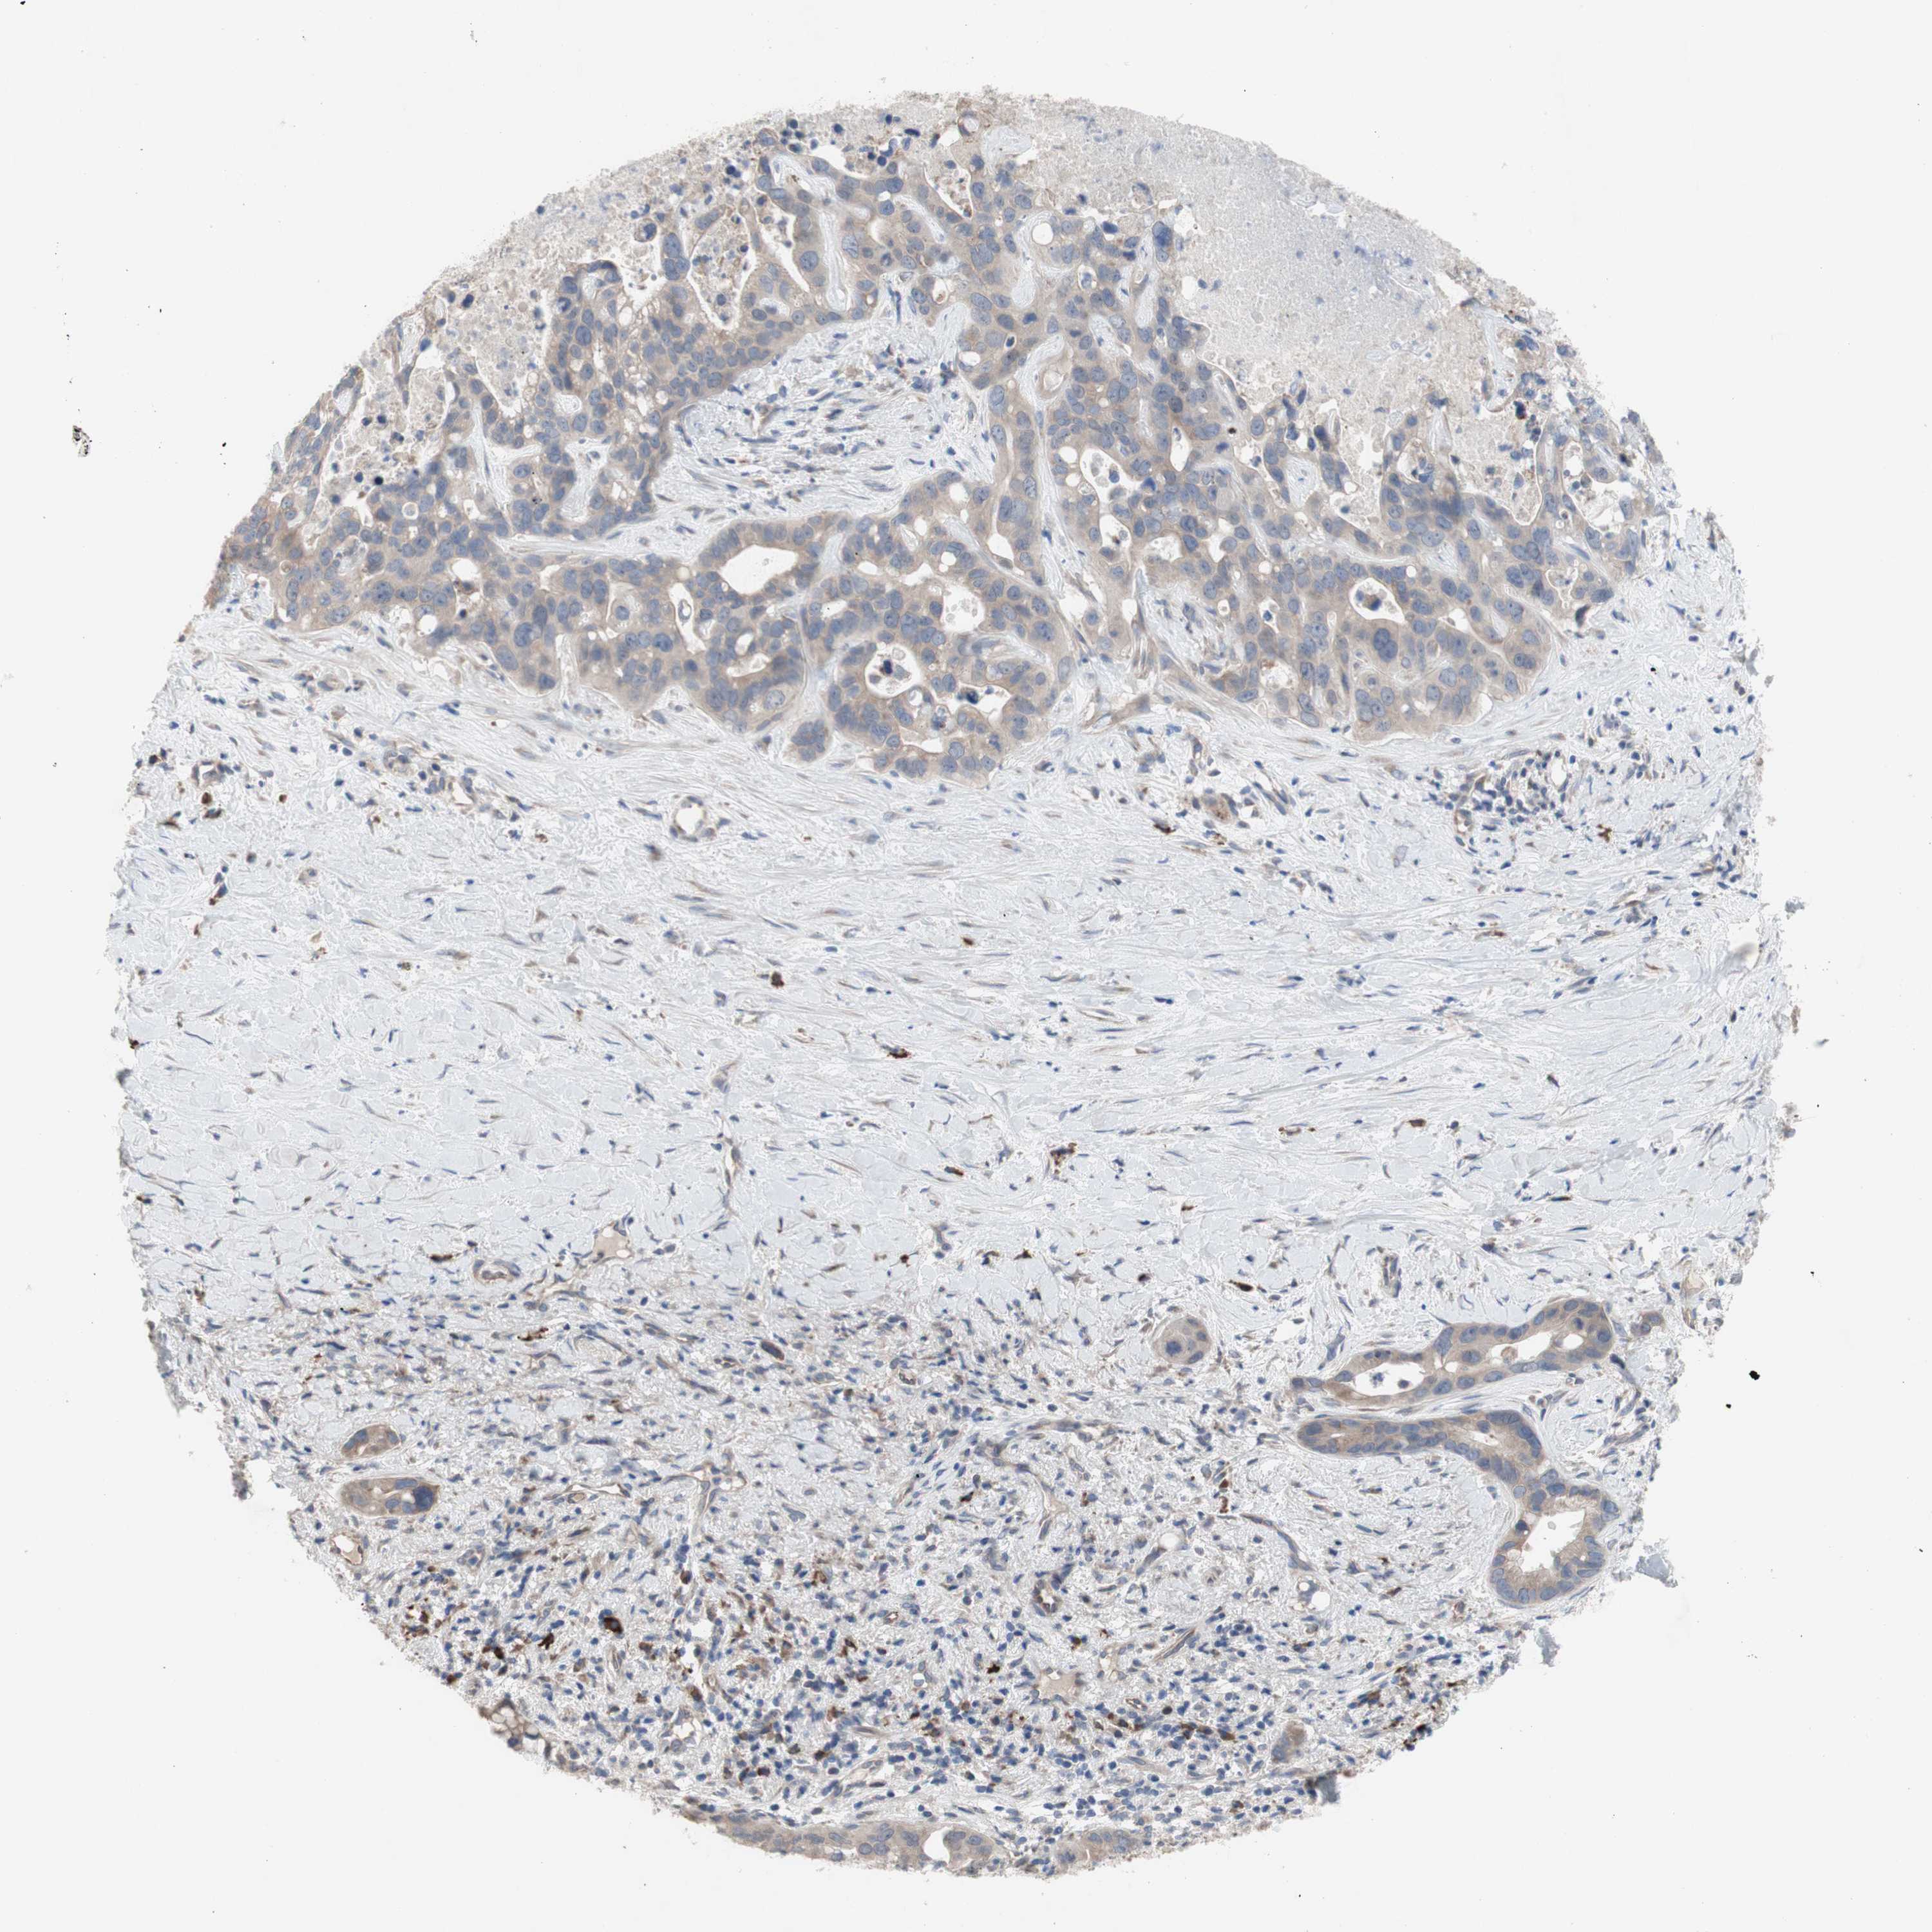

LIVER CANCER - Protein expressioni

A mouse-over function shows sample information and annotation data. Click on an image to view it in a full screen mode. Samples can be filtered based on level of antibody staining by selecting one or several of the following categories: high, medium, low and not detected. The assay and annotation is described here.

Note that samples used for immunohistochemistry by the Human Protein Atlas do not correspond to samples in the TCGA dataset.

Antibody stainingi

Antibody staining in the annotated cell types in the current human tissue is reported as not detected, low, medium, or high, based on conventional immunohistochemistry profiling in selected tissues. This score is based on the combination of the staining intensity and fraction of stained cells.

Each image is clickable and will lead to virtual microscopy that enables deeper exploration of all samples and also displays staining intensity scores, fraction scores and subcellular localization as well as patient and tissue information for each sample.

Antibody HPA009295

Staining

High

Medium

Low

Not detected

Intensity

Strong

Moderate

Weak

Negative

Quantity

>75%

75%-25%

<25%

None

Location

Nuclear

Cytoplasmic/membranous

Cytoplasmic/membranous,nuclear

Cholangiocarcinoma

Carcinoma, Hepatocellular, NOS